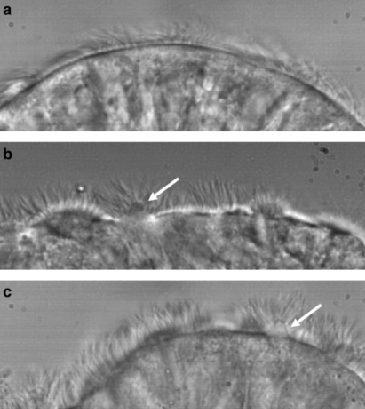

3. High-Speed Videomicroscopy (HSVM)

HSVM evaluates ciliary beat pattern and frequency using samples obtained from nasal or bronchial brushings. When performed by experienced specialists using validated SOPS, abnormal motility patterns can provide strong evidence for a PCD diagnosis. However, HSVM is highly operator-dependent; interpretation by inexperienced personnel can lead to both false positives and false negatives. In North America, HSVM is used as an adjunctive diagnostic test and in research. It is not used alone to diagnose PCD.